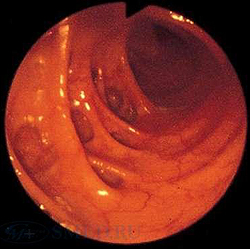

Колоноскопия является основным методом диагностики дивертикулита. Данное исследование позволяет провести дифференциальную диагностику заболевания с неспецифическим язвенным колитом, запорами, кишечной непроходимостью и опухолью толстого кишечника. Во время эндоскопии толстого кишечника при дивертикулите обнаруживаются поврежденные устья дивертикулов с воспалением слизистой оболочки вокруг них. Исследование дает возможность уточнить локализацию кровоточащих участков и оценить интенсивность кровотечения.

- Кишечная эндоскопия. Использование эндоскопических методов диагностики (колоноскопия, ректороманоскопия) показано только после купирования признаков воспаления. Колоноскопия является незаменимым методом поиска источника кровотечения, однако может способствовать появлению осложнений заболевания. Преимуществом эндоскопических методик является возможность проведения биопсии, морфологического исследования биоптатов.